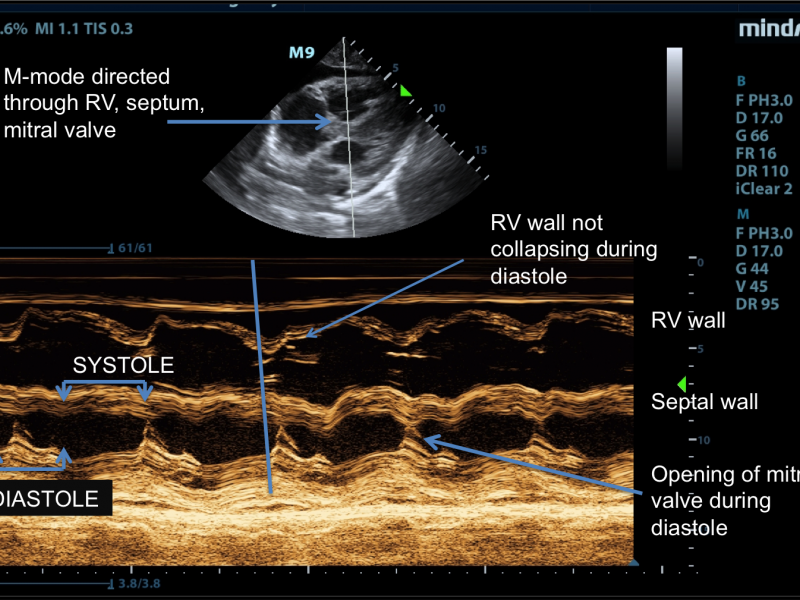

Cardiac Tamponade

June 21 2017

A patient in the ICU reports worsening shortness of breath